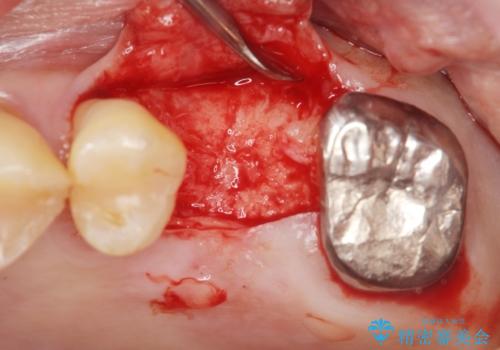

奥歯のインプラント ソケットリフト 60代男性

- 奥歯のインプラントをご希望し、来院された患者様です。

精査したところ上顎骨の厚みが薄かったため、ソケットリフト(上顎洞底挙上術)を併用してインプラント治療を行いました。